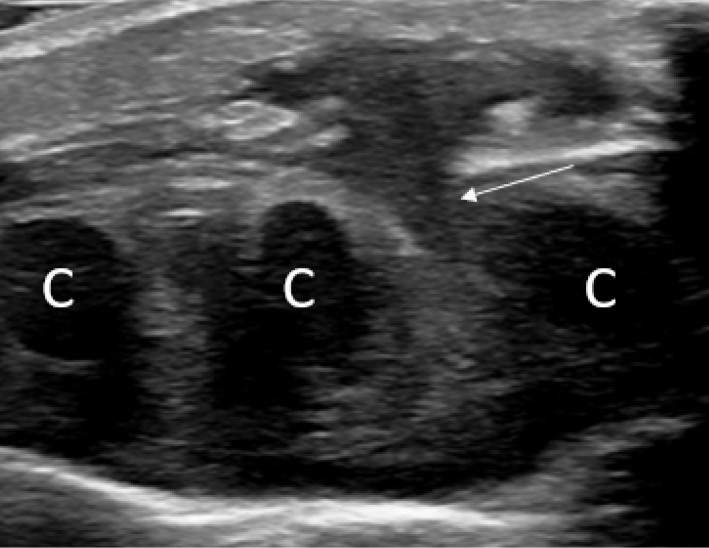

教学点:在血液结果正常且胸骨肿胀迅速增长且无创伤和全身性炎症疾病的婴儿中建立对儿童期自限性胸骨肿瘤(SELSTOC)的认识。

Teaching point: Creating awareness of self‑limiting sternal tumour of childhood (SELSTOC) in infants with rapidly growing sternal swelling with normal blood results and without trauma and systemic inflammatory diseases.